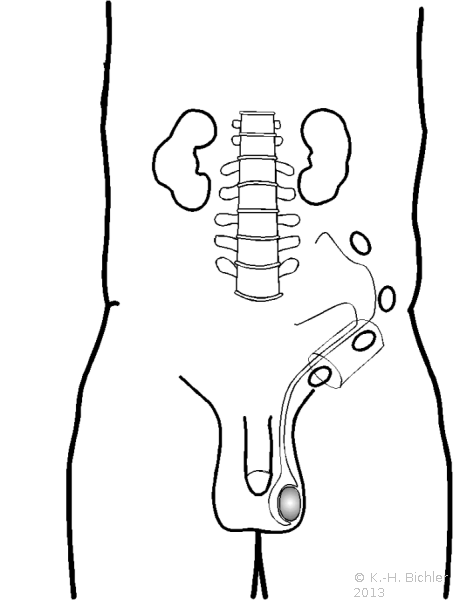

Diagnostisches und therapeutisches Vorgehen bei nicht palpablen Hoden:

Abbildung 6.